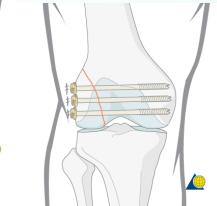

Locked Compression Plate (LCP):

- Has a combination hole:

- Oval hole for compression or ordinary screw

- Serrated hole for locked-head screws

- Advantages:

- More resistant to failure from screw loosening and pullout

- Very good fixation in osteoporotic bone

- Plate does not press on bone (preserves periosteal blood supply)

- Indications:

- Fracture of osteoporotic bone

- Bridging severely comminuted fractures